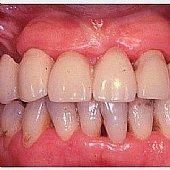

• Provisorische Versorgung des Oberkiefers nach Extraktion in einem Seitenzahnbereich. Deutlich ist der Weichgewebs-Effekt zu den Zähnen im Seitenzahnbereich zu erkennen.

• Provisorische Versorgung des Oberkiefers nach Zahnfleisch-Transplantation. Die Defekte sind verschwunden und ausgeglichen.